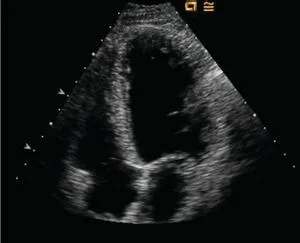

- 2D: a two-dimensional view of cardiac structures that can be visualized as time progresses (Figure 1.5).